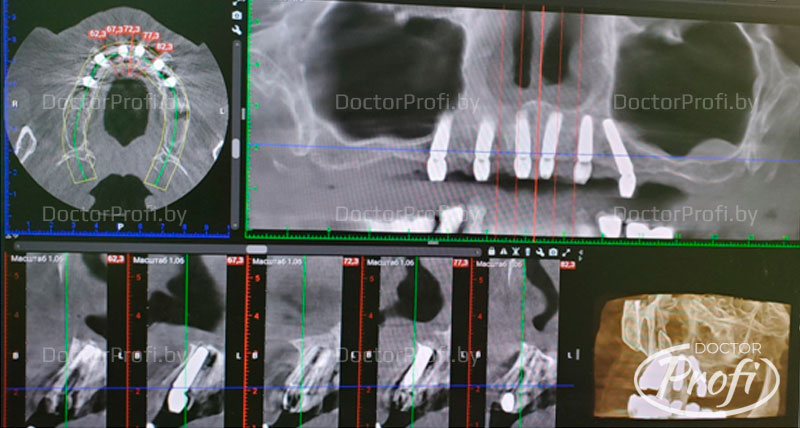

Анализ КЛКТ: атрофия костной ткани верхней челюсти в области 1.3,2.3 более 1/2 длины корней, в области 1.7,1.2,1.1,2.1,2.2 более 2/3 длины корней, киста верхнечелюстной пазухи слева.

- Пациентке была проведена санация верхней челюсти, удалены зубы 1.7,1.3,1.2,1.1,2.1,2.2,2.3 с одномоментной установкой шести имплантов Megagen AnyOne в области 1.5,1.3,1.1,2.1,2.3,2.5 под немедленную нагрузку.